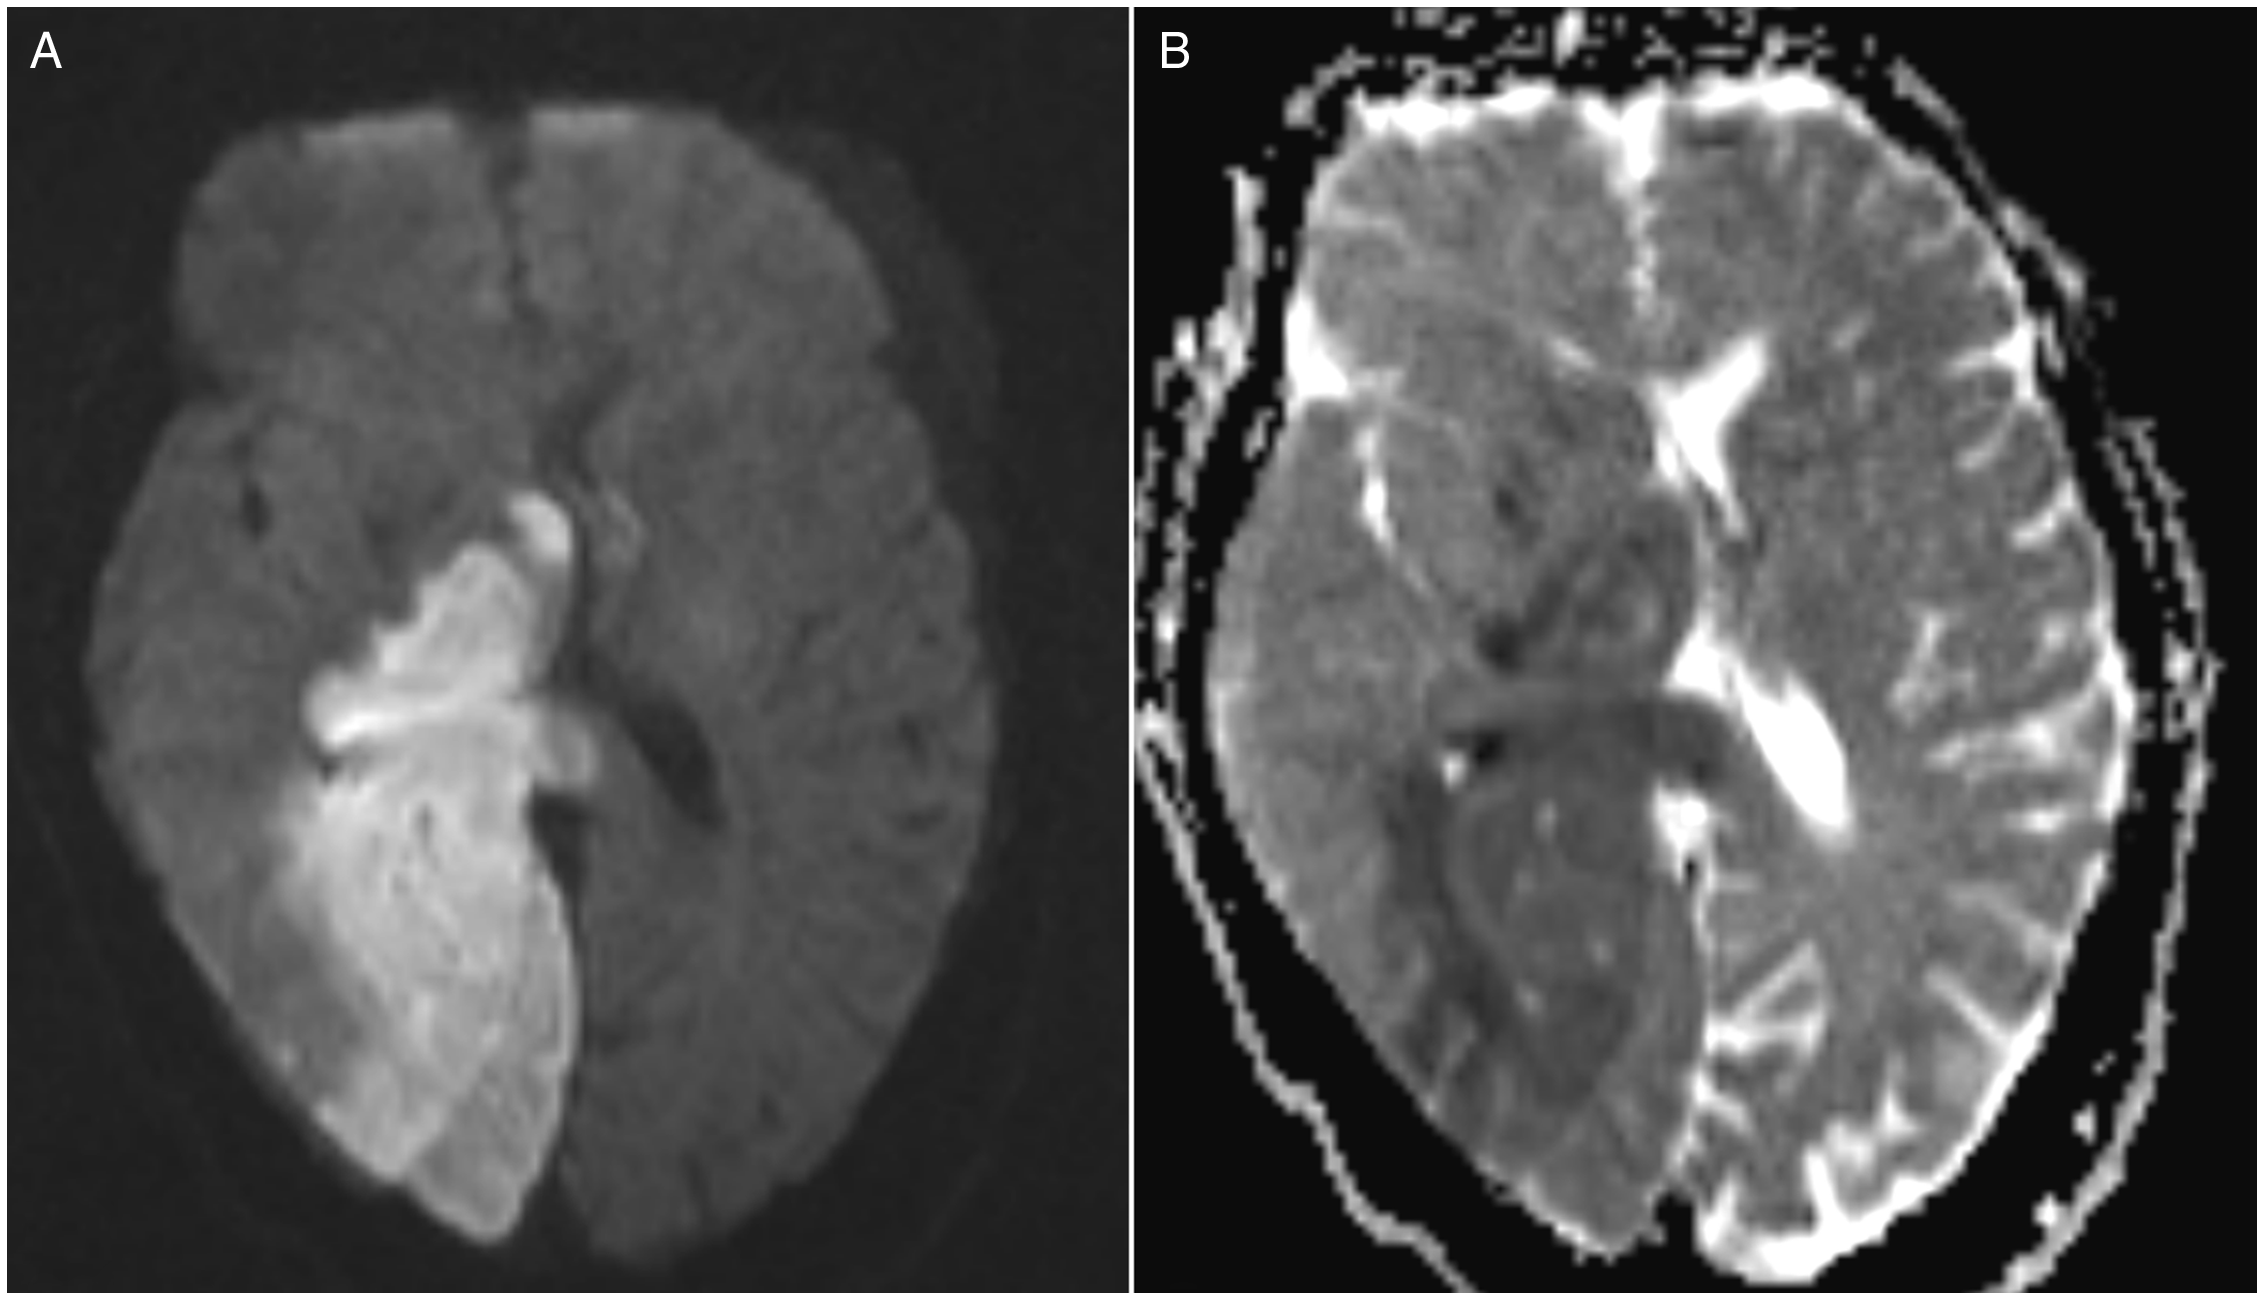

A 70-year-old woman with dyslipidemia, longstanding smoking, and known bilateral carotid stenosis (left >70% and right 50–70%) presented with acute onset left hemiparesis, left hemianesthesia with tactile neglect, rightward gaze deviation, and left homonymous hemianopia. Her initial National Institute of Health Stroke Scale score was 12. Noncontract CT head exhibited early ischemic changes in the right posterior cerebral artery (PCA) territory. CT perfusion imaging demonstrated established core tissue in the right PCA territory congruent with ischemic changes on CT. Mean transit time was increased in both the right PCA and middle cerebral artery (MCA) territories. CT angiogram demonstrated occlusions in the proximal right internal carotid artery (ICA), right persistent trigeminal artery (PTA), and P1/P2 junction of the right PCA (Figure 1C and D). Thrombolysis and endovascular thrombectomy were not pursued due to the amount of established infarcted tissue and being outside the thrombolytic time window. Follow-up MRI revealed restricted diffusion in the right PCA territory (Figure 2).

Figure 2: Right posterior cerebral artery infarction secondary to thromboembolic occlusions via persistent trigeminal artery (PTA). Axial diffusion-weighted (A) and ADC (B) MRI demonstrating right PCA territory infarction.